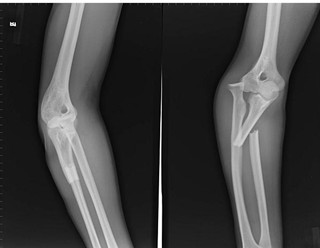

•   右肘关节恐怖三联症

发布时间:16-05-11 来源:台州黄岩新安康复医院 阅读66次

导读: 基本信息:吴先生,男,37岁 患者不慎摔伤致右肘关节肿痛伴活动障碍入院,X线片示右肘关节恐怖三联症。转上海市第六人民医院行右肘关节骨折切开复位…